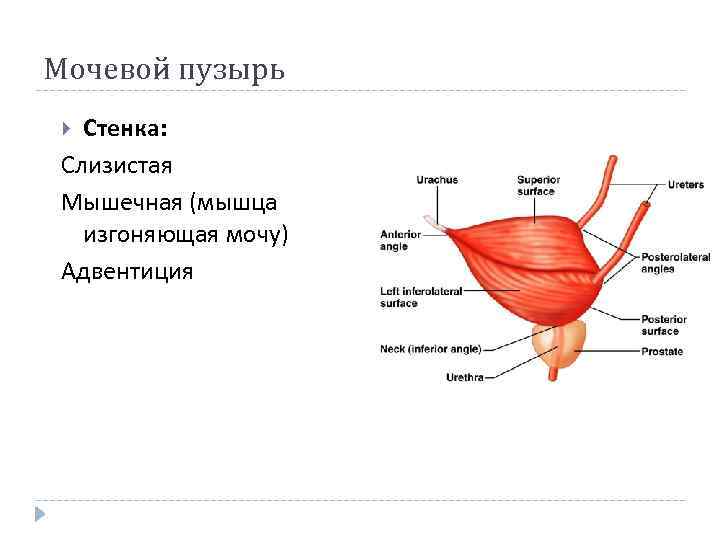

Мочевой пузырь Стенка: Слизистая Мышечная (мышца изгоняющая мочу) Адвентиция

Мочевой пузырь Стенка: Слизистая Мышечная (мышца изгоняющая мочу) Адвентиция